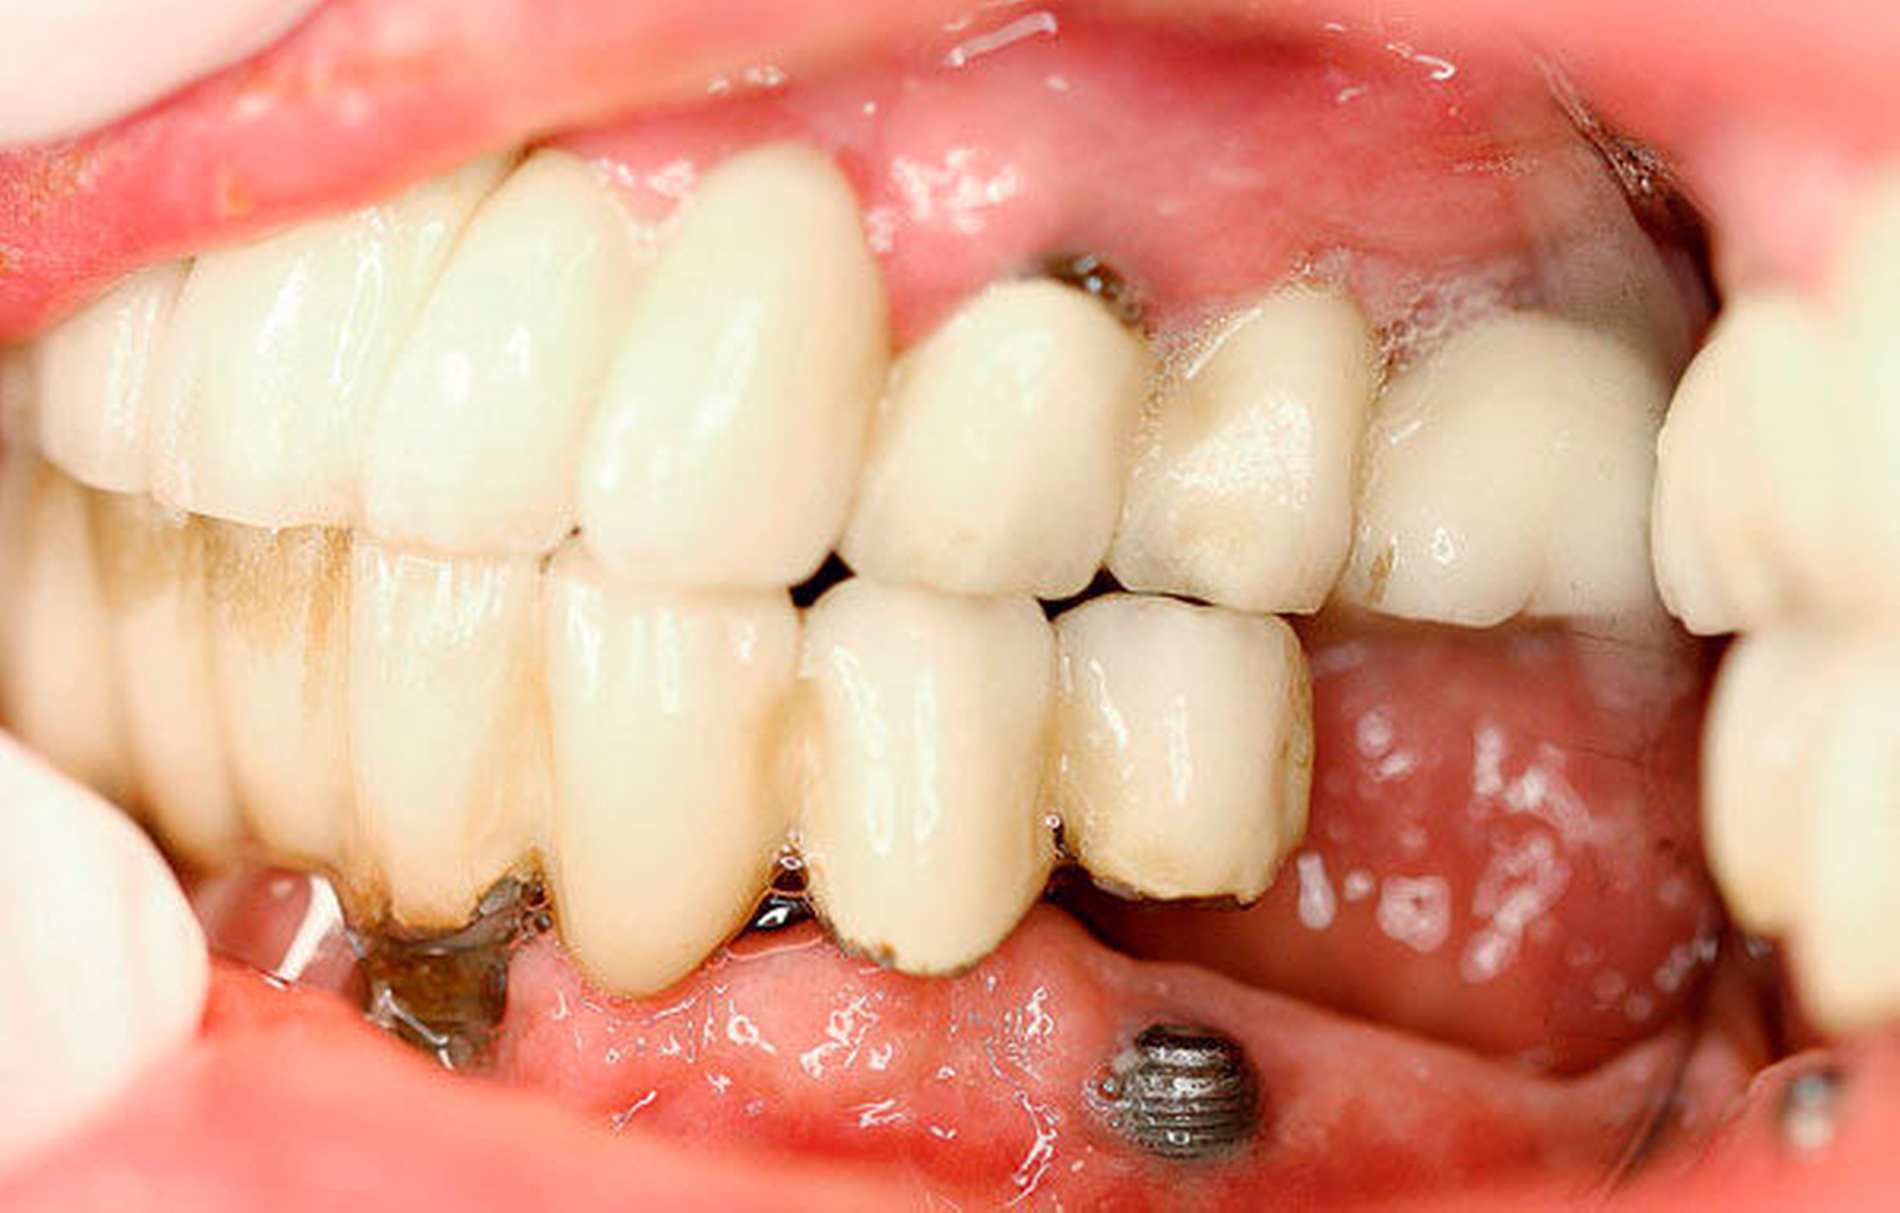

Intraoral zeigten sich implantatgetragene Kronen-Brückenkonstruktionen im Ober- und im Unterkiefer. Diese waren initial sowohl im Ober- als auch im Unterkiefer auf jeweils vier Implantaten befestigt. Im Bereich des rechten Oberkiefers zeigte sich in Regio 16 eine Mund-Antrum-Verbindung, die offenbar nach dem Versuch einer primären plastischen Deckung weiterbestand. Es bestand eine breite Dehiszenz bis ins Kieferhöhlenlumen hinein. An allen Implantaten zeigte sich eine chronische Periimplantitis mit ausgeprägtem Knochenabbau und freiliegenden oberen Gewindegängen.

Im vorliegenden Fall stellte sich der 50-jährige Patient elf Jahre nach implantatprothetischer Versorgung nach dem All-on-4 Konzept vor. Das Konzept „All-on-4“ mit einer festsitzenden Versorgung ist gut dokumentiert [Balshi et al., 2014]. Malo et al. konnten den Erfolg und die Ergebnisse über zehn Jahre verfolgen und dokumentieren [Malo et al., 2011]. Die Datenlage scheint so gut, dass das beschriebene Konzept manchen Autoren zufolge einer aufwendigen Sinuslift-Behandlung vorzuziehen ist [Asawa et al., 2015]. Bei hoch atrophierten Kiefern ist ein extralanges Zygoma-Implantat eine gute Option und kann gute Ergebnisse liefern [Brånemark et al., 2004].

Das Problem beim Einbringen der Zygoma-Implantate ist die korrekte Positionierung in den Jochbeinkörper. Hier kann es besonders beim liegenden Patienten leicht zu einer Via falsa kommen. Im vorliegenden Fall wurden die 60 mm langen Zygoma-Implantate statt in den Jochbeinkörper beidseits in die Orbita gesetzt. Das Problem der möglichen Fehlpositionierung langer Fixturen und von Zygoma-Implantaten wurde früh erkannt und es wurden hierfür Navigationshilfen entwickelt [Stella et al., 2000]. Schiroli et al. beschrieben 2011 eine Methode zur Computer-navigierten Insertion dieser Implantate. Sie wiesen auf der Basis ihrer Erfahrungen mit 25 Implantaten darauf hin, dass Komplikationen auch mit der Navigation nicht vollständig ausgeschlossen werden können [Schiroli et al., 2011].